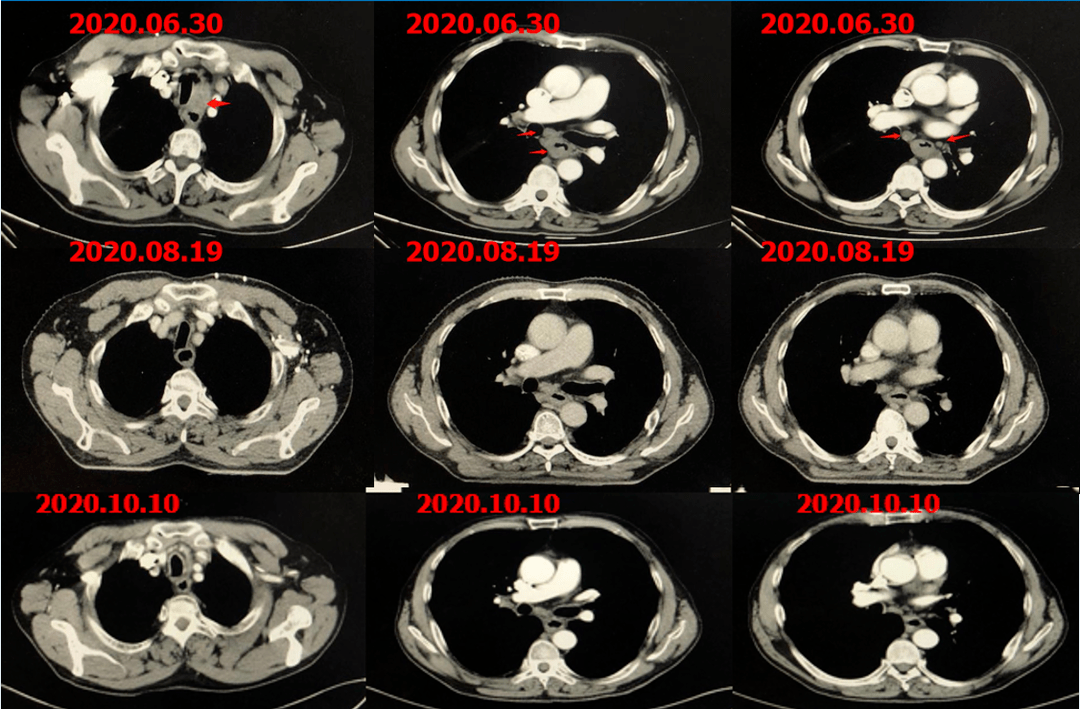

结合影像检查结果(胸部增强ct,pet-ct)提示食管肿瘤及淋巴结明显缩小

图片尺寸942x954